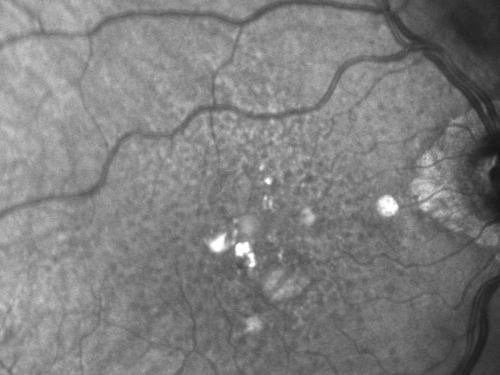

Reticular Macular Disease (Pseudo-drusen) Both Eyes - Wet AMD OS - Dry AMD OD InfraRed

84-year-old woman has wet age-related macular degeneration in the left eye and dry macular degeneration in the right eye.  She takes the eye vitamins and her vision is stable since she was treated three months ago with Avastin.   OD 20/50,  OS 20/32